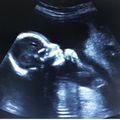

Идёт 8 неделя, а у меня то низ живота болит , то одно , то второе. И токсикоз уже как неделю не беспокоит, только грудь тут на днях болела просто до слез!( сейчас намного лучше, но низ все равно при напряжении как простреливает. Говорят связки.И в связи … Читать далее